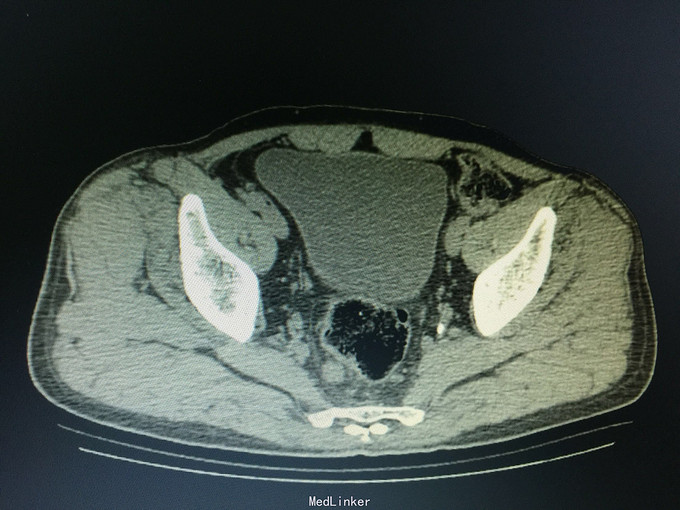

一般状态好,无贫血貌,肛门外缘不规整,肛门指诊:距肛缘4cm可及溃疡性肿物,近环形,固定,指套染陈旧血。 辅助检查:盆腔CT:直肠管壁不规则肥厚,官腔偏心性狭窄,周围见条索影及结节影。

诊断:直肠癌, 预约结肠镜检查:距肛缘4cm见环肠肿物,凸凹不平,表面覆污秽苔,质硬,界不清。 病理结果为直肠腺癌。 病人回当地医院接受治疗。